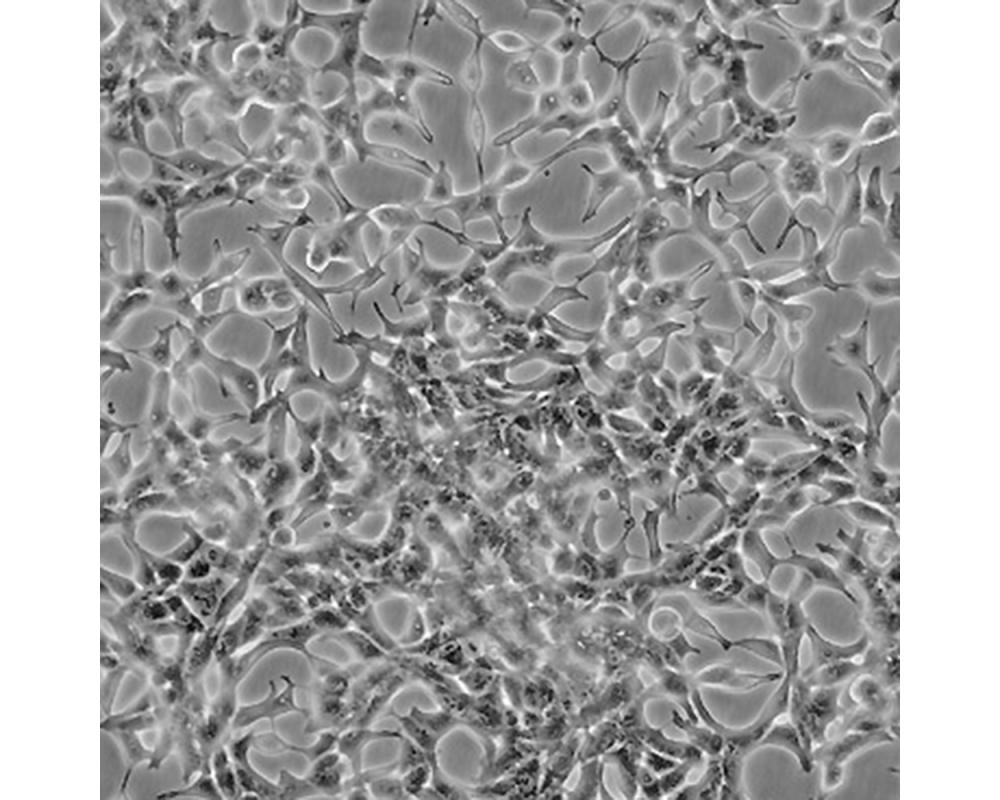

形態(tài)特征

上皮細(xì)胞

生長(zhǎng)特性

人前列腺癌細(xì)胞LNCaP克隆FGC是從一位50歲白人男性(血型B+)的左鎖骨淋巴結(jié)針刺活檢中分離,該患者經(jīng)確診為前列腺癌轉(zhuǎn)移。 這株細(xì)胞對(duì)5-α-二氫睪酮(生長(zhǎng)調(diào)節(jié)子和酸性磷酸脂酶產(chǎn)物)有響應(yīng)。 這株細(xì)胞并不形成一致的單層,而是形成集落,在傳代時(shí)可以用滴管反復(fù)吹吸打碎。 它們僅僅輕輕地吸附在基底上,不形成匯合,很快使培養(yǎng)基變酸。 生長(zhǎng)很慢。 傳代后48小時(shí)內(nèi)不應(yīng)擾動(dòng)。 當(dāng)培養(yǎng)瓶封包后,多數(shù)細(xì)胞從培養(yǎng)瓶底分離,懸浮在培養(yǎng)基中。 收到后,在通常培養(yǎng)單層細(xì)胞的條件下培養(yǎng)24到48小時(shí),以合細(xì)胞再貼壁。